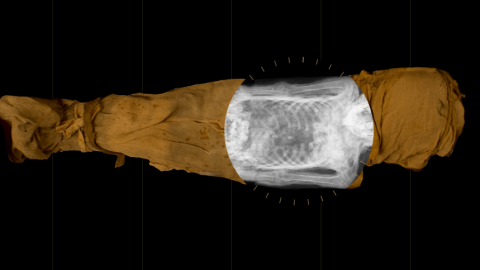

Image of the mysterious lady of the National Museum in WarsawWarsaw Mummy Project